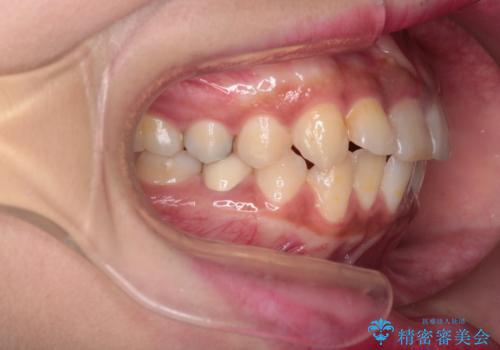

- 患者様は、前歯の突出感を気にされて来院されました。診察の結果、歯列のスペースが不足しており、前歯を後方へ移動させるには抜歯が必要と判断。上下の小臼歯4本を抜歯し、目立ちにくい審美ワイヤー矯正(白いワイヤーと透明ブラケット)を使用して治療を行う計画を立てました。

抜歯によって前歯を下げるためのスペースを確保。その後、審美ワイヤー矯正を用いて、歯列全体のバランスを整えながら前歯を後方へ移動させました。治療後は、横顔のラインが整い、自然な口元になったことで、見た目も噛み合わせも改善しました。患者様からは「口元がすっきりして、自信を持って笑えるようになった」と喜びの声をいただきました。